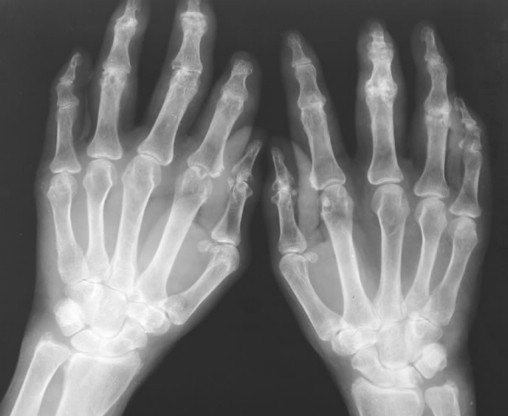

风湿性关节炎会导致关节破坏:患者关节损害主要表现为骨质疏松明显,关节间隙轻度狭窄。早期仅有关节间隙狭窄,严重者关节面边缘模糊不清,凹凸不平或囊状透亮区。关节严重破坏期患者有多处软骨下骨破坏,关节畸形明显狭窄,关节变形。关节间隙尚可见,骨质疏松明显。推荐文章:有什么和风湿性关节炎的发病有关

关节破坏严重可导致关节强直,此期关节表现为关节间隙完全消失,关节融合。可见粗条的骨小梁通过关节面,大关节可见骨质增生或硬化表现。关节间隙融合或纤维性强直。关节强直占风湿性关节炎总数的1%,通常发生于风湿性关节炎晚期,患者除典型风湿性关节炎临床表现外,还可表现为脾脏肿大和白细胞减少及血小板减少。白细胞减少的原因或为脾功能亢进,或存在骨髓抑制因子等。风湿性关节炎伴发淀粉样变性常见于风湿性关节炎晚期,淀粉样变见于脾脏、肾、胃肠道及全身小血管等部,是预后不良的征象之一。